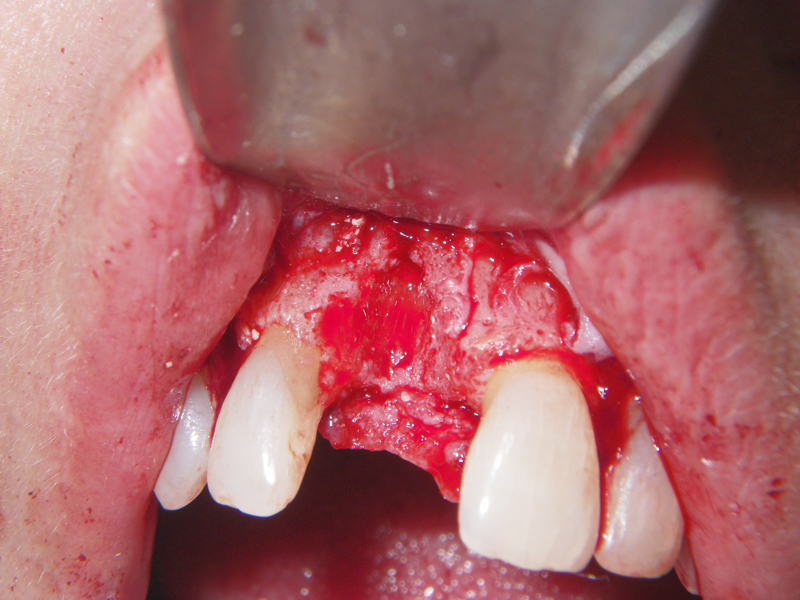

- Stage I: Implant placement/Sealing Screw

- Alveolar Ridge Augmentation

- Blockgraft